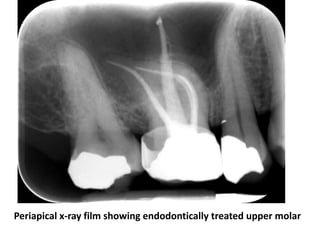

Periapical x-ray film showing endodontically treated upper molar

• Is removal of vital or necrotic pulp tissue from

pulp chamber and root canal by cleaning

and shaping process

• Then the chamber and canal cavities must be

blocked by suitable sealing materials to not

become a shelter of pathogens “hermetic

seal”